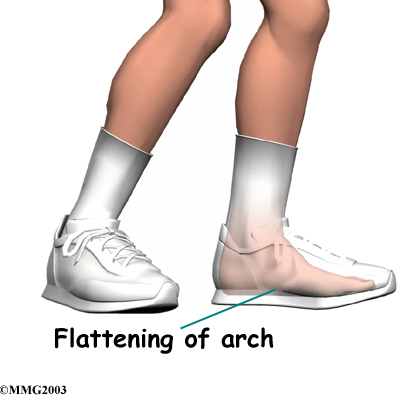

Posterior shin splints are generally caused by imbalances in the leg and foot. Muscle imbalances from tight calf muscles can cause this condition. Imbalances in foot alignment, such as having (called pronation), can also cause posterior shin splints. As the foot flattens out with each step, the posterior tibialis muscle gets stretched, causing it to repeatedly tug on its attachment to the tibia. The posterior tibialis muscle attachment eventually becomes damaged, leading to pain and inflammation along the inside edge of the lower leg.

Posterior shin splints are generally caused by imbalances in the leg and foot. Muscle imbalances from tight calf muscles can cause this condition. Imbalances in foot alignment, such as having (called pronation), can also cause posterior shin splints. As the foot flattens out with each step, the posterior tibialis muscle gets stretched, causing it to repeatedly tug on its attachment to the tibia. The posterior tibialis muscle attachment eventually becomes damaged, leading to pain and inflammation along the inside edge of the lower leg.

Foot Support

Your Ari Levine PT, PC specialist will evaluate your posture and alignment to see if you have problems with pronation (arch flattening), a condition that we commonly see associated with posterior shin splints. Sometimes a small heel wedge, placed under the inside edge of the heel, is enough to ease tension on the posterior tibialis muscle. For more severe problems of pronation, we may recommend foot orthotics to support the arch and reduce stresses on the posterior tibialis muscle.